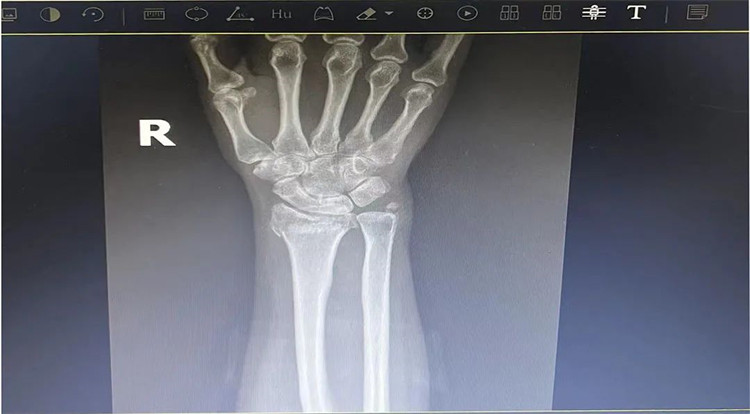

患者基本情況

患者老年女性,50多歲,在騎電動車停下時因電動車倒下,右手著地,當(dāng)即感覺,右腕及骶尾部腫痛伴右關(guān)節(jié)畸形、活動受限,急來我院就診。門診醫(yī)師結(jié)合病史、查體及輔助檢查后,診斷為:右橈尺骨遠(yuǎn)端骨折、骶尾部挫傷并收入住院部。